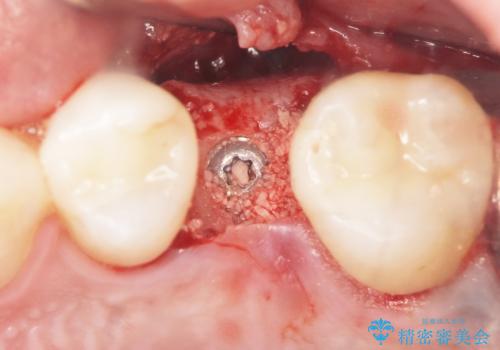

前歯は被せものをやり替えるだけでよいかのように見えますが、見えない部分で外部吸収が進行し、歯が虫食い状に吸収されてしまっています。残念ながら、外部吸収が深い位置で進行すると、吸収性の組織を取り除く意義も兼ねて、抜歯が第1選択となってしまいます。

右上の前歯は部分矯正により歯を引っ張り出すことでなんとか保存しています。

仮歯・部分矯正・抜歯など、山口先生にて処置をされ、最終的な完成のみ引き継がせていただきました。今後はマウスピースの装着・スーパーフロスによる清掃などを継続していっていただく必要があります。